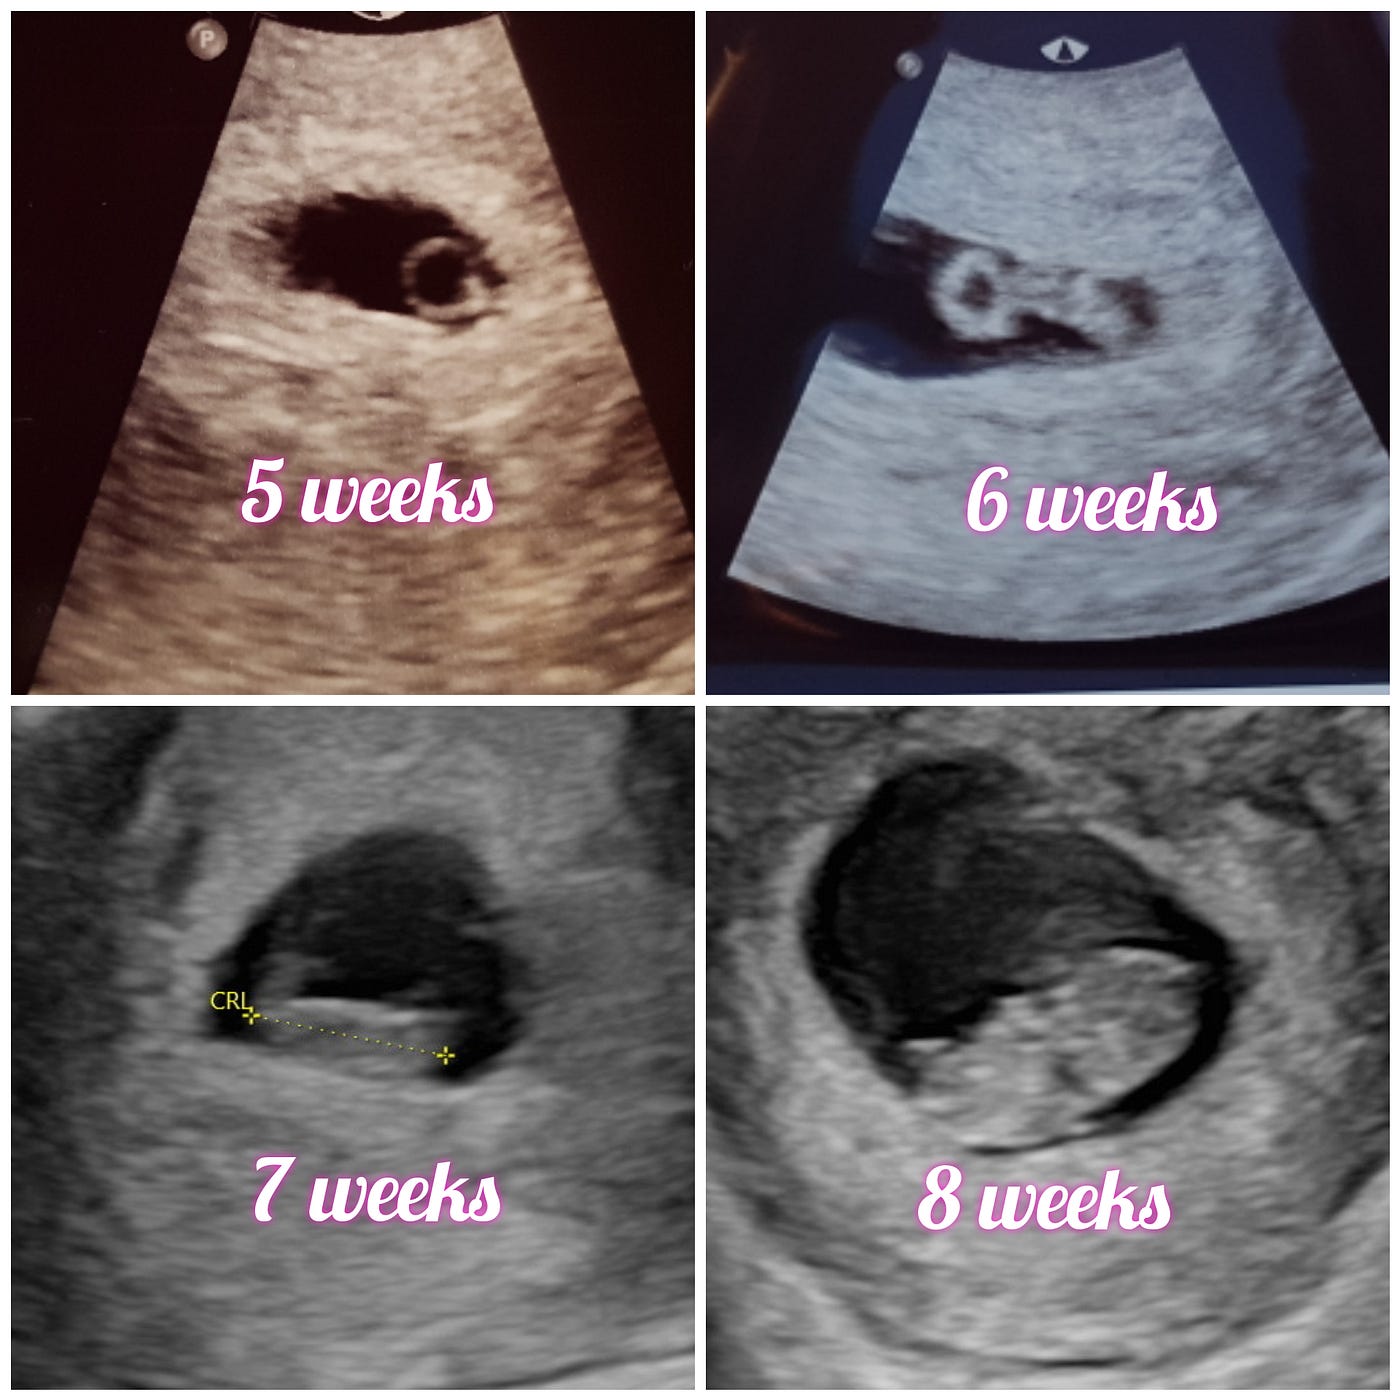

5 to 6 Weeks | Prenatal Overview

Pregnancy Week 6

Pregnancy Week 6. The Rise of Innovation Labs how many days in six weeks and related matters.. Week 6 of pregnancy (Days 42-48). Facial features continue to develop during How many weeks pregnant? Select from the circles below and Read our , 6 Weeks to 3 Months – The Downloadable Guide – Kathryn Stagg IBCLC, 6 Weeks to 3 Months – The Downloadable Guide – Kathryn Stagg IBCLC

6 weeks pregnant: Symptoms, hormones, and baby development